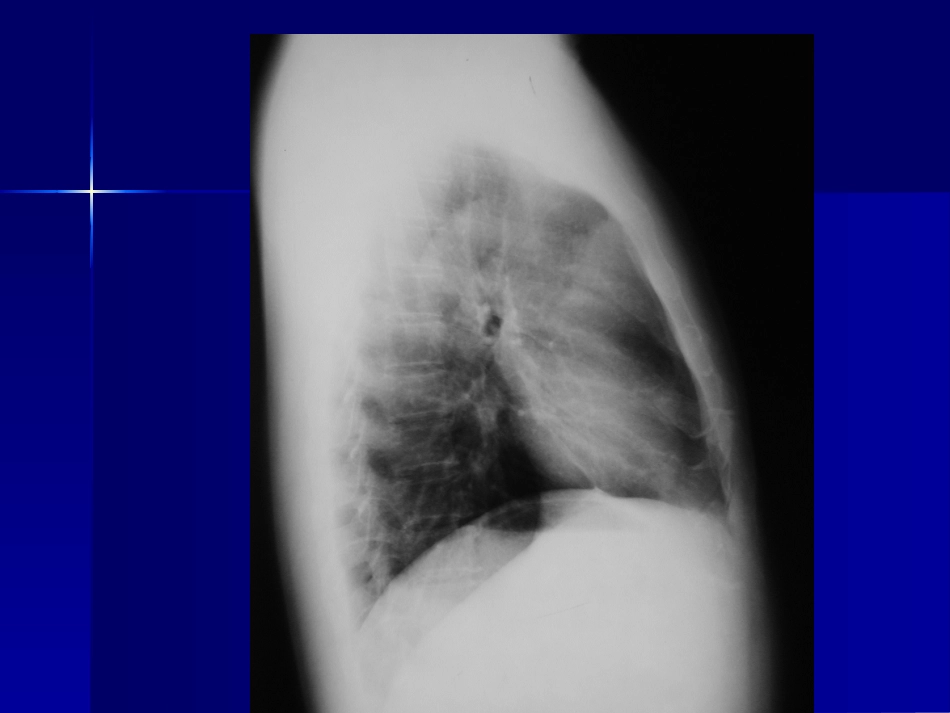

病例一病例一男,男,5252岁,体检发现前纵岁,体检发现前纵隔肿物隔肿物2020余天,胸闷、无余天,胸闷、无力,低烧十余天,抗炎治力,低烧十余天,抗炎治疗后好转。疗后好转。04-03-1104-03-11病理结果:右肺上叶尖段病理结果:右肺上叶尖段及纵隔慢性肉芽肿性炎症,及纵隔慢性肉芽肿性炎症,考虑结核。考虑结核。病例二病例二男,男,5454岁,咳嗽胸闷一年岁,咳嗽胸闷一年半,咳血半,咳血2020余天。余天。04-02-2704-02-2704-02-2604-02-26病理结果:病理结果:右肺下叶内基底段炎性假瘤右肺下叶内基底段炎性假瘤病例三病例三男,42岁,咳嗽一月余,无发热,咳血04-03-0504-03-05抗炎治疗一周后,病灶明抗炎治疗一周后,病灶明显缩小变淡。显缩小变淡。诊断:右肺下叶球性肺炎诊断:右肺下叶球性肺炎病例三病例三男,男,4646岁,岁,02-11-0402-11-0402-11-02-11-0404病理结果:管状—绒毛状病理结果:管状—绒毛状腺瘤腺瘤病例四病例四男,男,3434岁,发现腹部肿岁,发现腹部肿物一月。物一月。04-02-1804-02-1804-02-2604-02-26病理结果:肝左叶肝癌病理结果:肝左叶肝癌